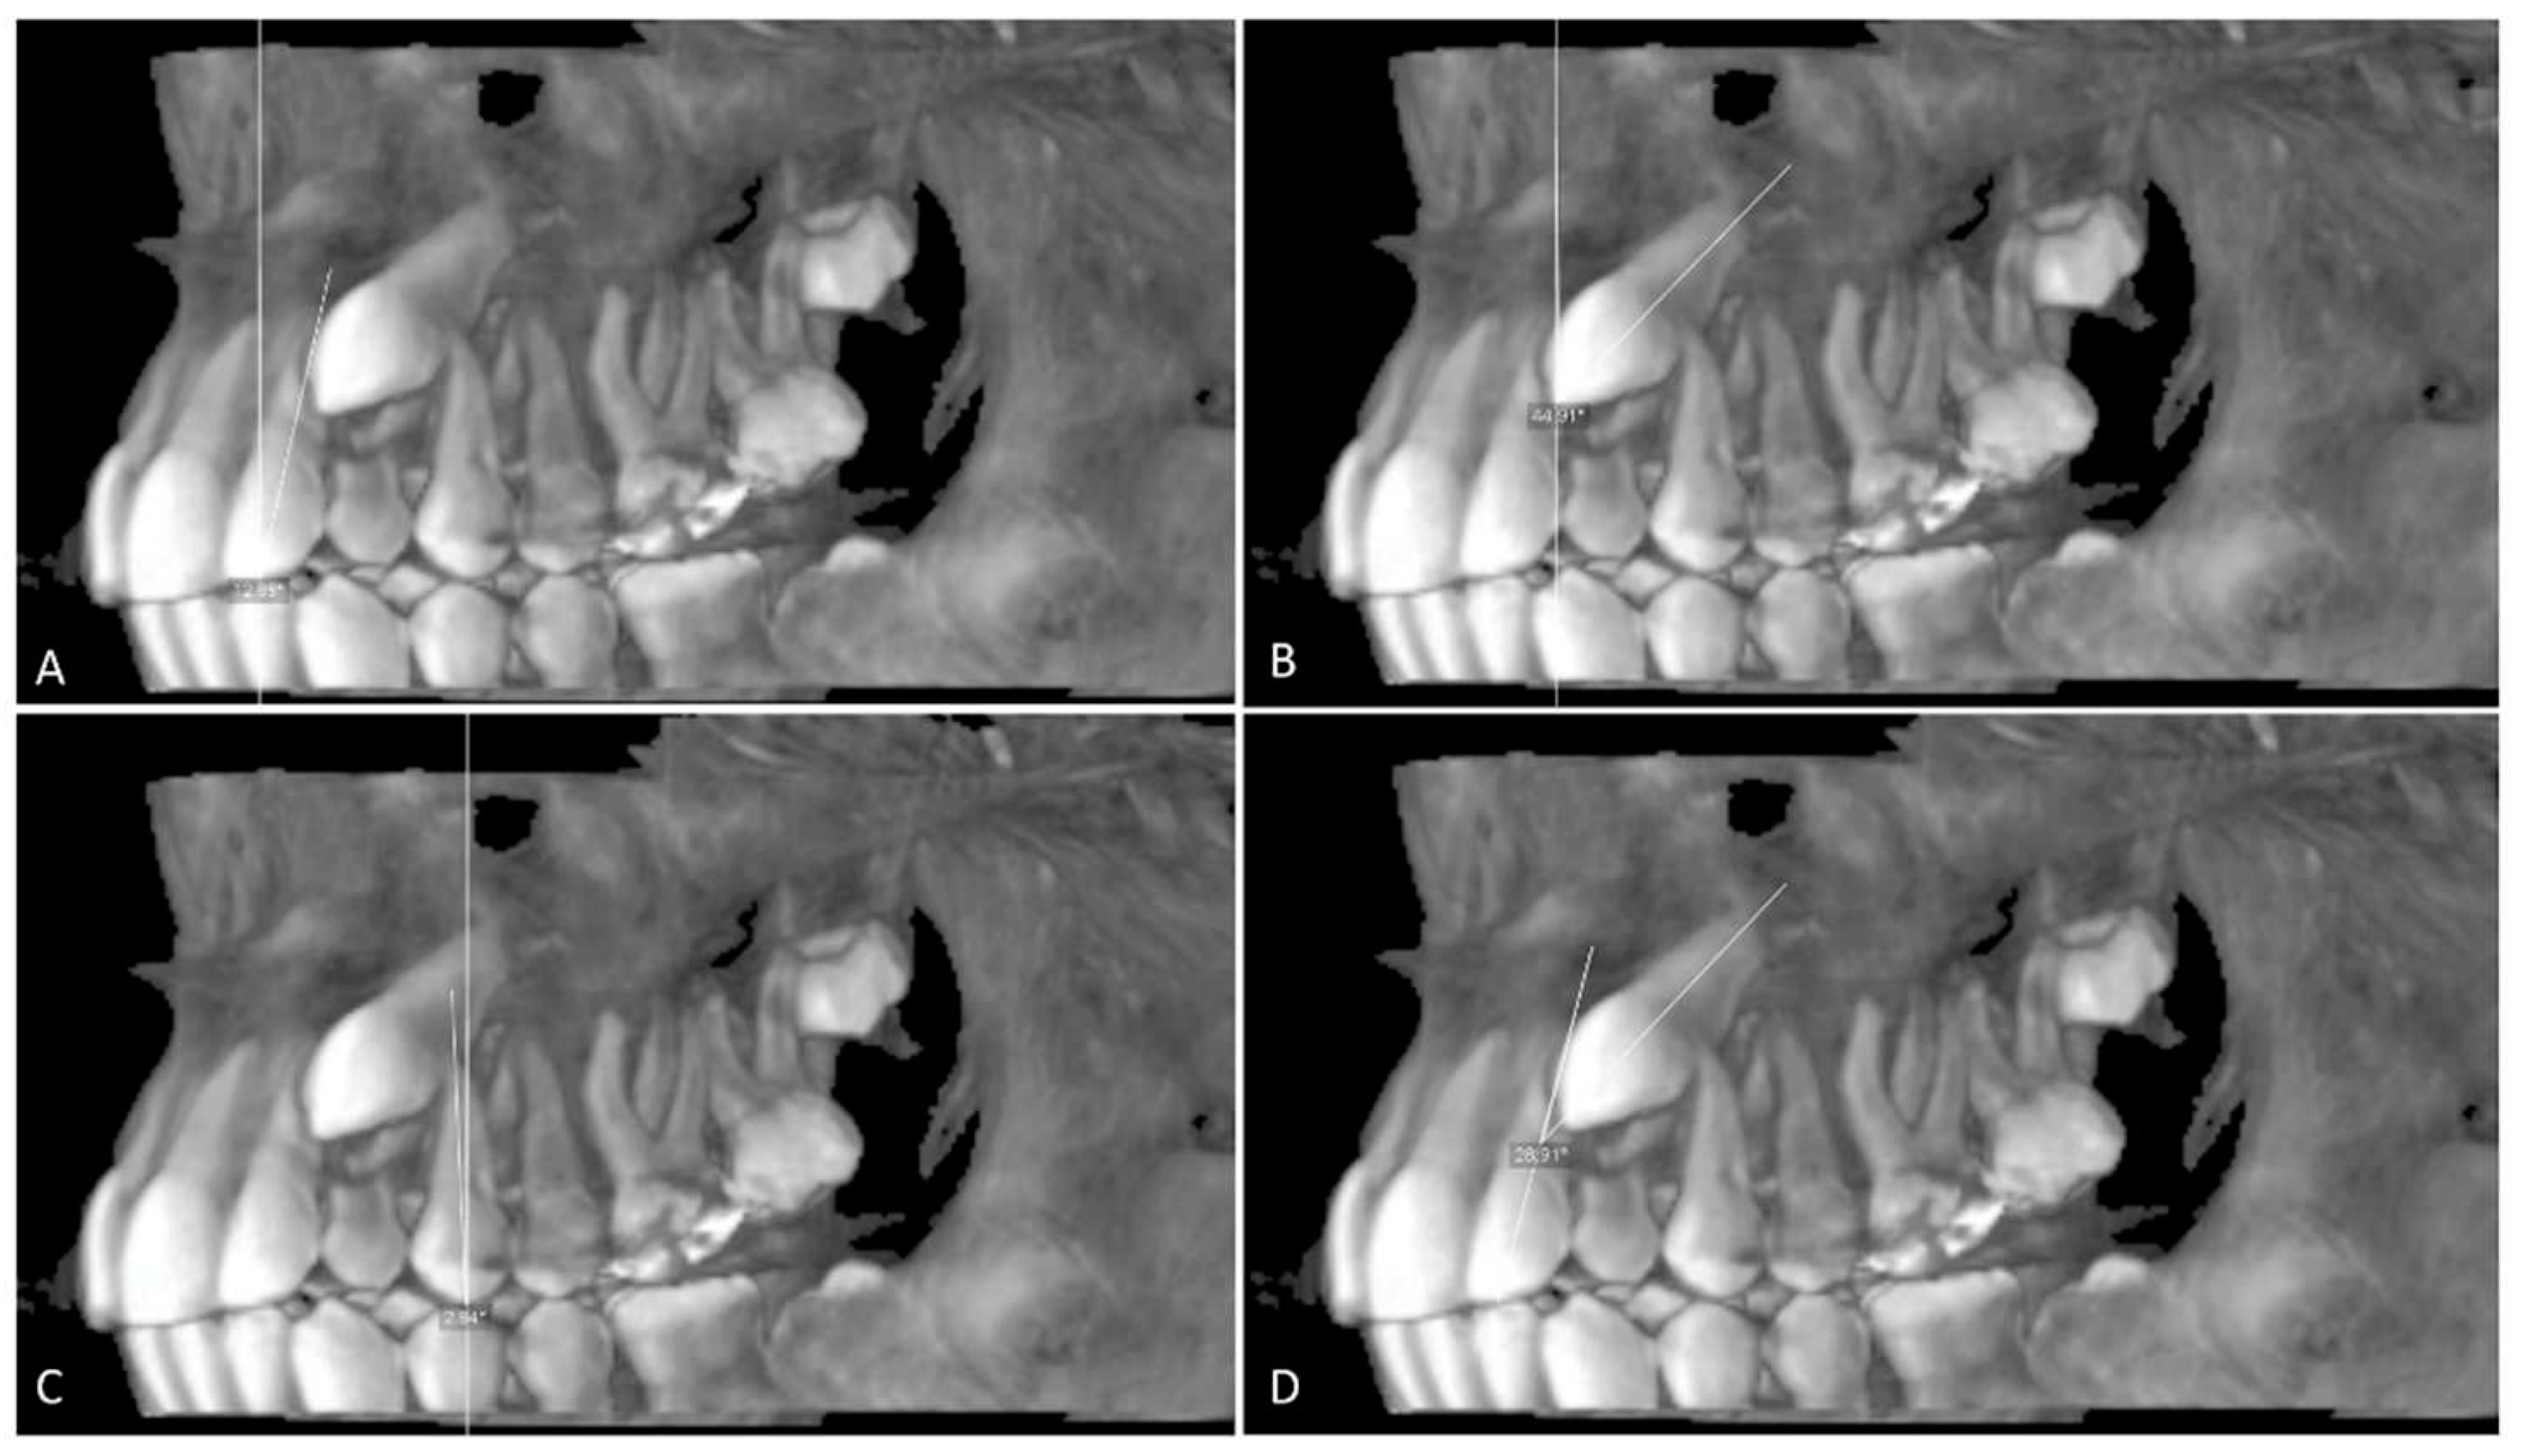

The buccolingual (BL) and mesiodistal (MD) widths of the crowns of the lateral incisor (U2) and canine (U3) were measured from the widest point of the crown perpendicular to the long axis on the sagittal and coronal sections, respectively (Figure 4 and Figure 5).

Root length (RL) was measured from the lowest level of the buccal cementoenamel junction (CEJ) to the root apex, and the total length (L) of the lateral incisor was measured from the incisal tip to the root apex on the sagittal section (Figure 5). The horizontal distance of the maxillary impacted canine (U3 HD) from the tip of the canine cusp to the midline was measured in the axial section. The vertical distance of the maxillary impacted canine (U3 VD) from the tip of the canine cusp to the occlusion plane was measured in the sagittal plane (Figure 4, Figure 5 and Figure 6).

Figure 4. A. Mesiodistal width of the canin crown (U3 MD) and B. Mesiodistal width of the lateral crown (U2 MD); the distance between widest points of the crown on the axial section. C. Horizontal Distance to midline from canine crown (U3 HD); distance from cusp tip of canine crown to the midline on the axial section.